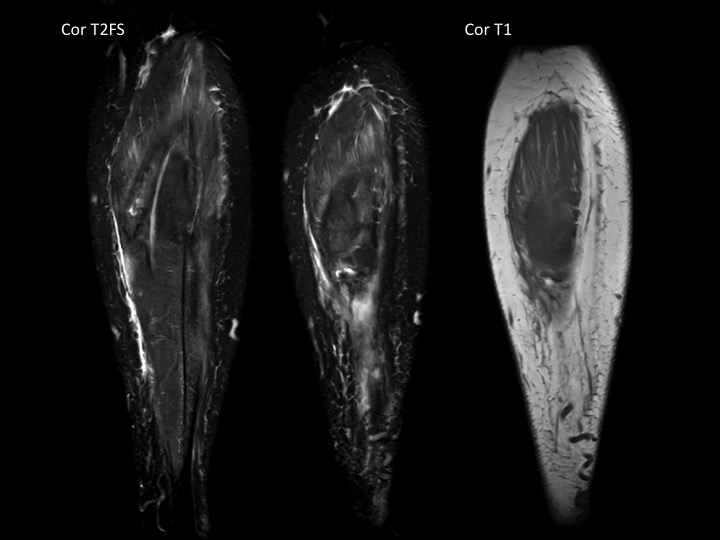

60F 3 weeks calf pain, suspect DVT

No DVT. Very subtle subacute full thickness tear at the distal myotendinous junction of the medial head gastrocnemius with 1.5 cm retraction at the tear and mild muscle edema. There is a subacute hematoma in the intermuscular fat planes (outlined in yellow) which is almost isointense to muscle, with a dark rim on ax T2FS and peripheral bright rim on T1. Easy to miss. Reference article.

medial head of gastrocnemius muscle ( RID2921 )